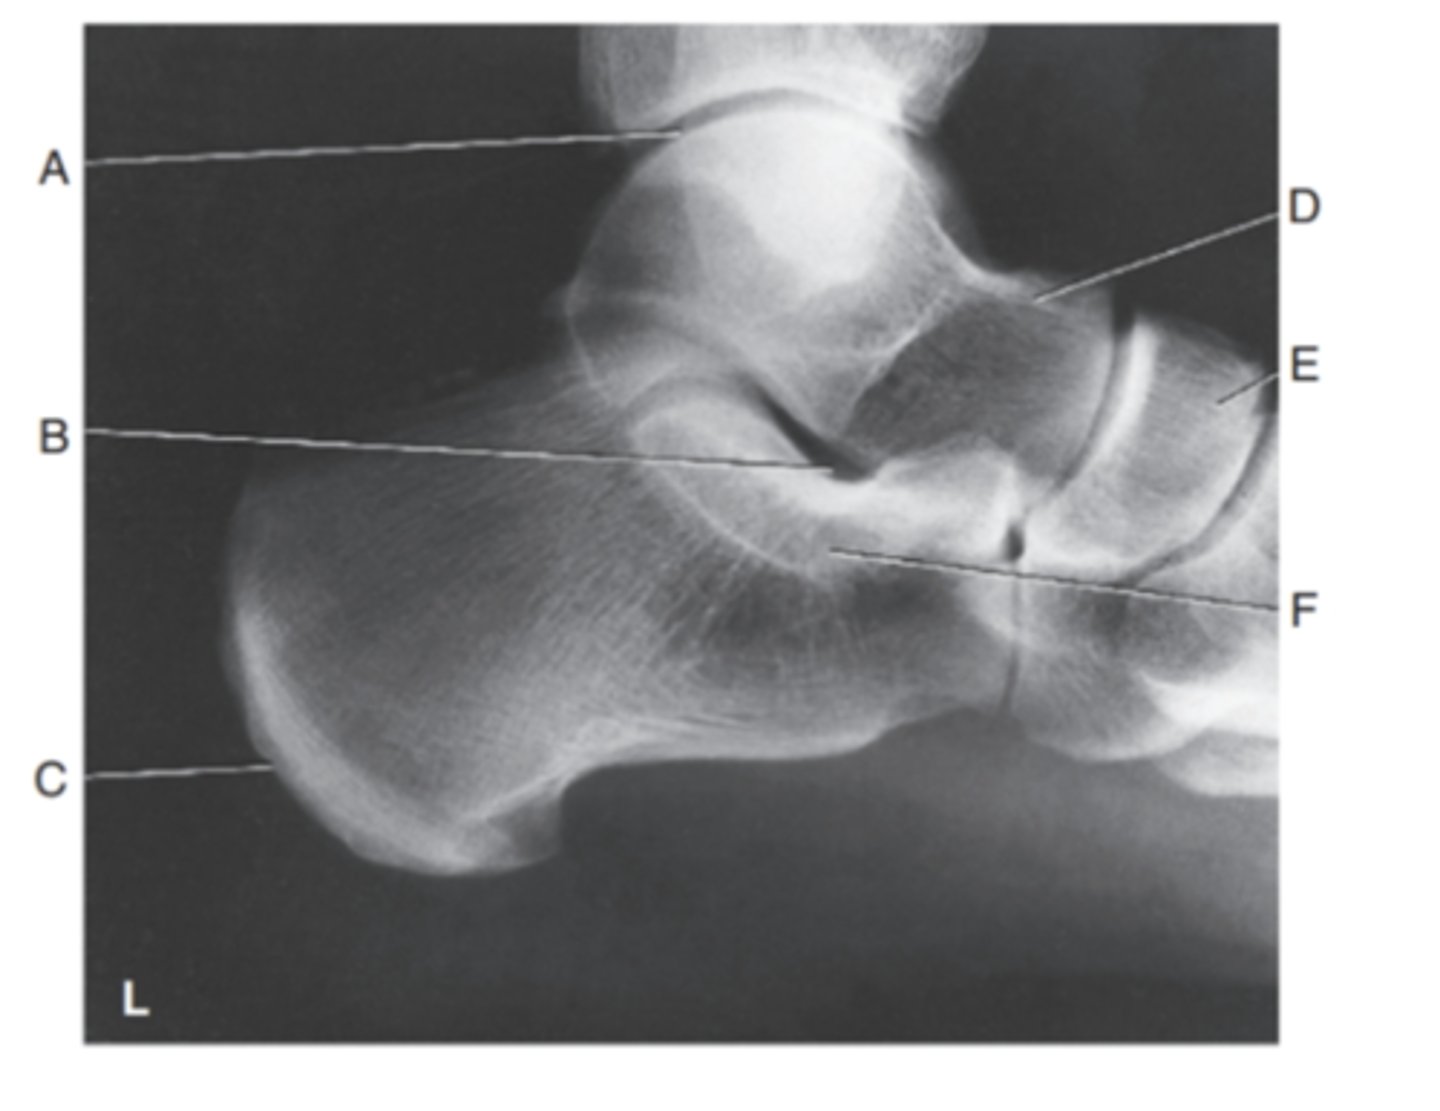

(LATERAL CALCANEUS) what is A?

tibiotalar joint

what is B?

sinus tarsi

what is C?

tuberosity

what is D?

talus

what is E?

navicular

what is F?

Sustentaculum tali